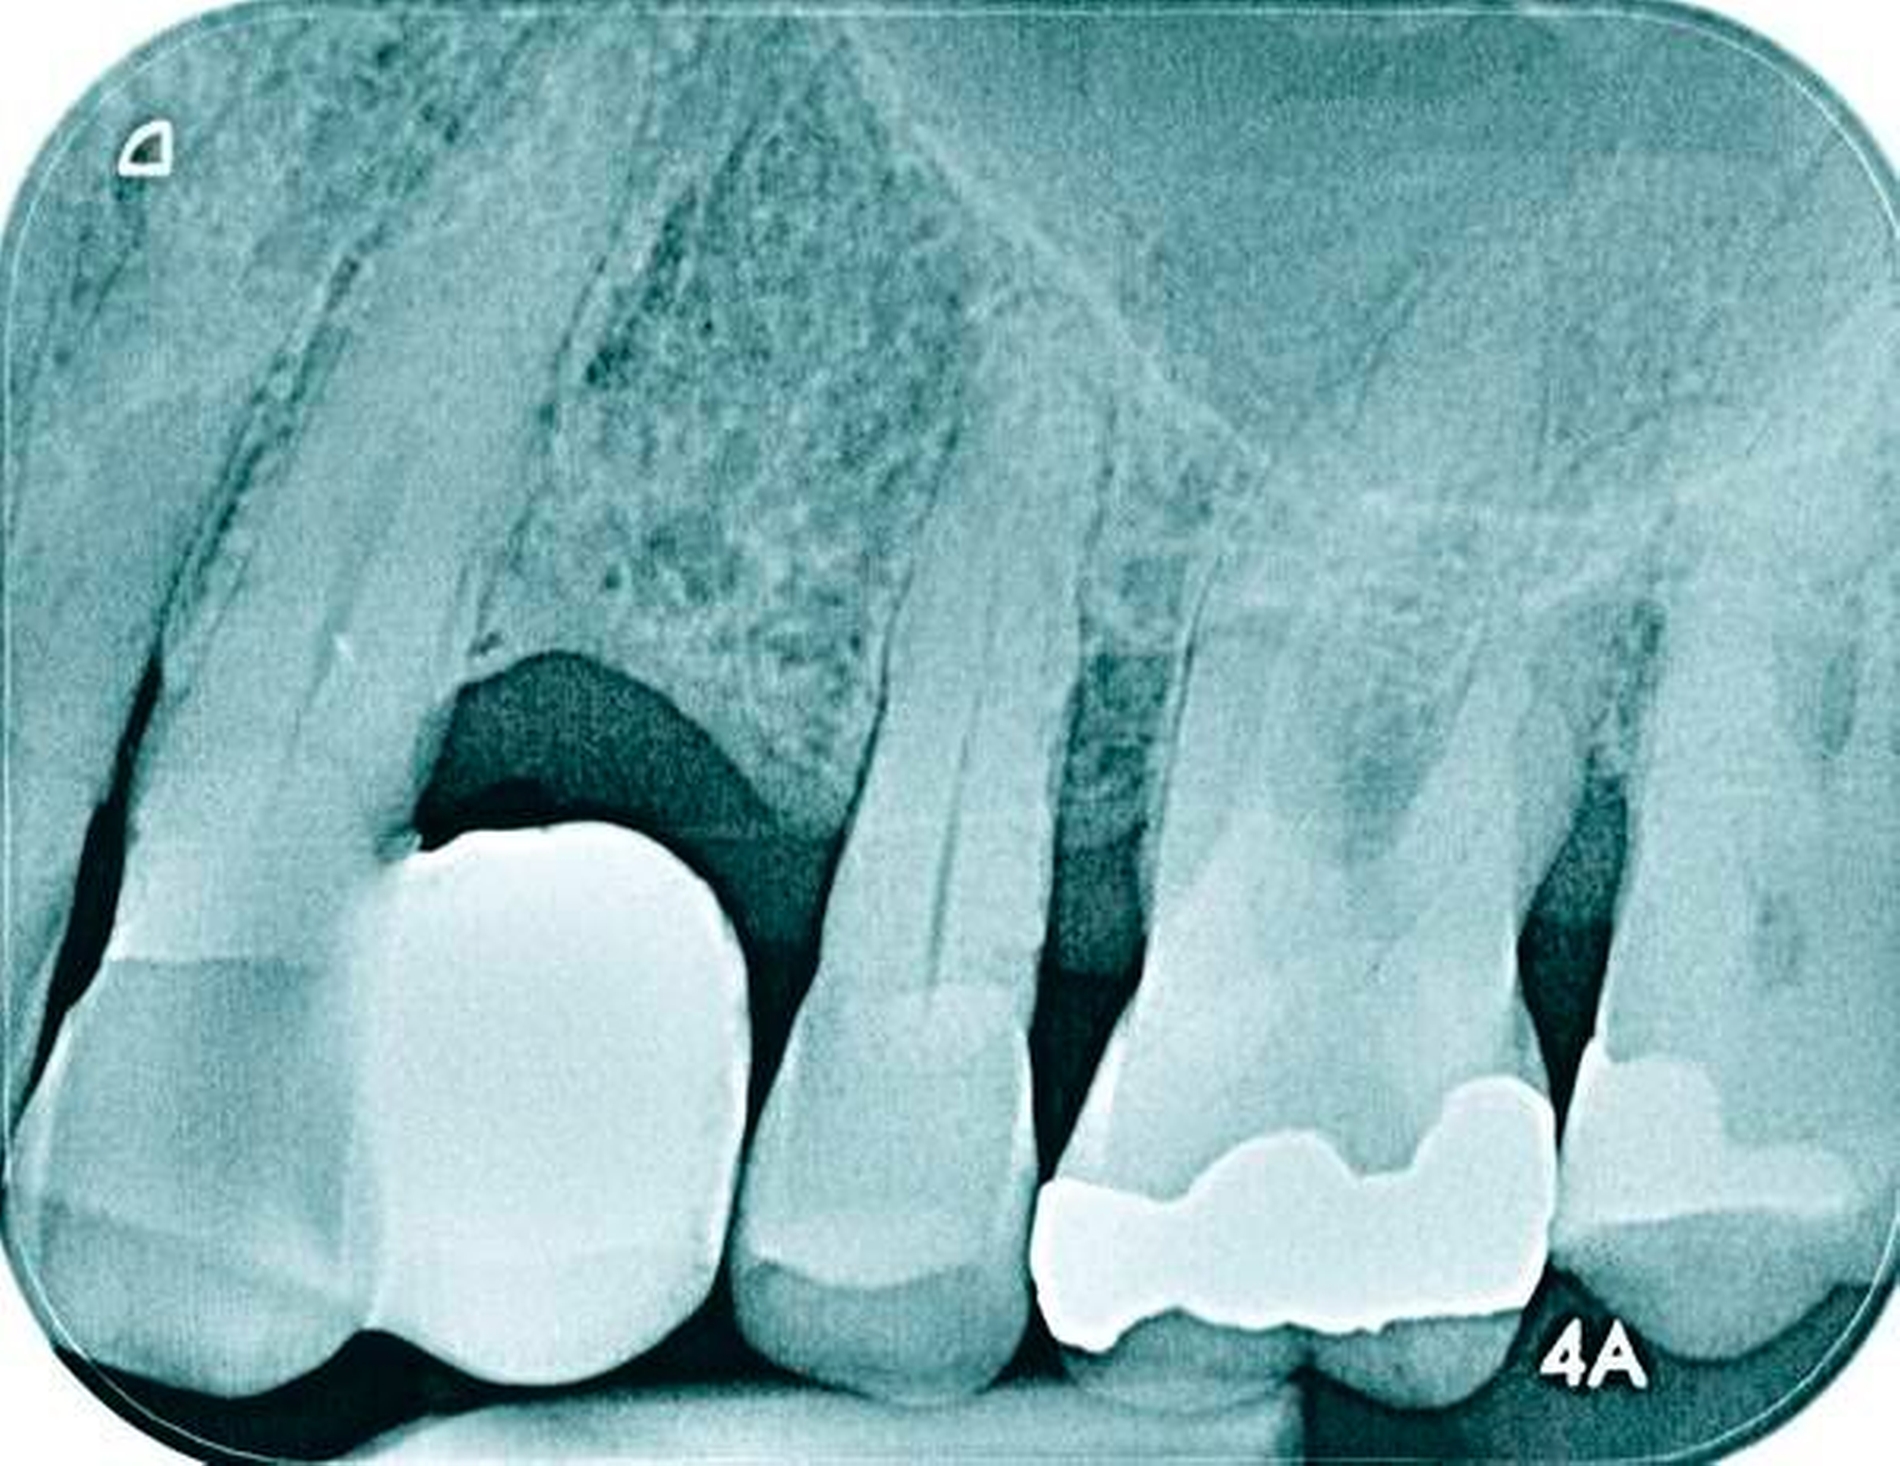

Abbildung 1a bis 1f: Direkte Überkronung im Frontzahnbereich (R1-Technik)

In den Abbildungen 1 bis 3 werden Optionen für frugale Interventionen auf restaurativem Sektor aufgeführt. Es handelt sich um direkte Vollüberkronungen im Frontzahnbereich (hier: hergestellt in R1-Technik / einphasig) (Abbildung 1), direkte Teilüberkronungen im Seitenzahnbereich (hier: hergestellt in R1-Technik / einphasig) (Abbildung 2), Reparatur-Restaurationen im Seitenzahnbereich (hier: hergestellt in R2-Technik / zweiphasig) (Abbildung 3). Technische Einzelheiten zur Vorgehensweise und den Ergebnissen sind an anderer Stelle beschrieben (Literatur siehe oben).

Am Beispiel von Abbildung 1 (stark zerstörte Zahnkrone eines Schneidezahns) kann das Prinzip der frugalen Intervention erläutert werden:

Früher wurde für die hier beschriebene Ausgangssituation folgendes Procedere gewählt:

Wurzelkanalbehandlung des vitalen Zahns als Voraussetzung für eine Stiftversorgung

Einsetzen eines Wurzelkanalstifts

Einsetzen einer indirekt gefertigten Stiftkrone

Durch die Erfolge der Adhäsiv- und Komposittechnik kann heute folgendermaßen vorgegangen werden:

Verzicht auf Wurzelkanalbehandlung / Erhaltung der Vitalität des Zahns

Verzicht auf Wurzelkanalstift

direkte minimalinvasive Kompositkrone (Verzicht auf indirekte Vorgehensweise)

Die potenziellen medizinischen und ökonomischen Vorteile dieser frugalen Intervention sind vielfältig:

Schonend: Die oralen Strukturen werden geschont und die Versorgung ist hinreichend stabil. Durch den Verzicht auf Wurzelkanalstifte wird das Wurzelfrakturrisiko reduziert. Zudem können Material-, Geräte- und Personalressourcen aus Praxis und Techniklabor, die beim klassischen Vorgehen anfielen, reduziert werden.

Bezahlbar: Hier ist anzumerken, dass die Kosten unter anderem von der zahnärztlichen Expertise abhängig sind: Zahnärzte, die mit direkten Restaurationen große Erfahrung haben, können zügiger und mit besserem Erfolg arbeiten als Kollegen mit geringerer Erfahrung auf diesem Gebiet; die Behandlung ist gleichwohl anspruchsvoll und deshalb nicht „billig“. Eine direkte Vorgehensweise kann, muss aber nicht automatisch zeit- und kostensparender sein als eine Versorgung mit indirekt hergestellten Werkstücken.

Gut genug: Ästhetische Feinheiten lassen sich bei direkten Restaurationen nicht immer in gleicher Perfektion einarbeiten wie bei indirekt gefertigten Kronen, auch die Stabilität des Hochglanzes lässt bei einigen Kompositpräparaten noch zu wünschen übrig. Andererseits erlauben die direkten Verfahren inzwischen mitunter sehr flexible Vorgehensweisen, die sich auch mit Farb- und Formkorrekturen von Zähnen kombinieren lassen. Die Erwartungen eines großen Teils der Patienten werden hinreichend erfüllt und die Nutzen-Risiko-Relationen wie auch die Aufwand-Kosten-Relationen erscheinen – wenn auch nicht durchgängig – so doch zumindest in vielen Fällen günstig.